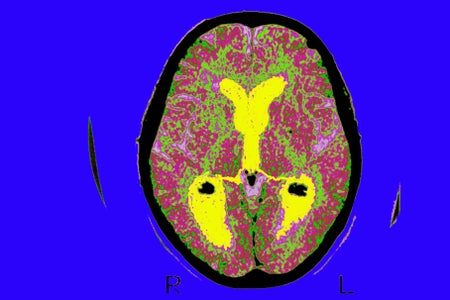

This Is Your Brain on Climate Change

Extreme heat caused by climate change can exacerbate a variety of neurological ailments, from Alzheimer’s disease to migraines to epilepsy, new research shows